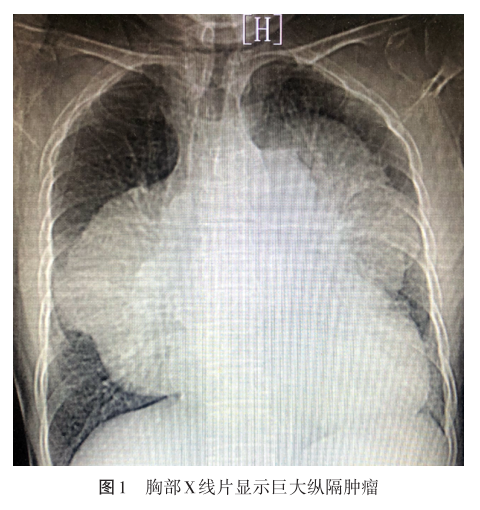

该患者既往类风湿性关节炎病史13年,现处于非急性期,不服药;28年前病毒性心肌炎病史,无后遗症。入院胸部X线片提示:巨大纵隔占位(图1)。胸部CT血管成像提示:

前纵隔囊实性占位(图2),考虑恶性肿瘤可能大;心包大量积液(图3);